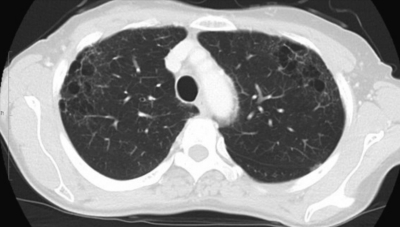

検査所見:血液所見:赤血球 350 万、Hb 9.8 g/dL、Ht 30 %、白血球 10,300、血小板 30 万。血液生化学所見:AST 19 U/L、ALT 15 U/L、LD 158 U/L (基準 176〜353)、γ-GTP 16 U/L (基準 8〜50)、総ビリルビン 0.4 mg/dL、総蛋白 7.2 g/dL、アルブミン 3.8 g/dL、尿酸 2.9 mg/dL、尿素窒素 11 mg/dL、クレアチニン 0.5 mg/dL、 Na 140 mEq/L、 K 4.0 mEq/L、 Cl 105 mEq/L、 Ca 8.9 mg/dL、Fe 20 μg/dL、TIBC 231 μg/dL (基準 290〜390)、フェリチン 643 ng/mL (基準 20〜120)、CEA 4.5 ng/mL (基準 5以下)。CRP 1.4 mg/dL。画像所見:上肺野(肺野条件)、中肺野(縦隔条件)、下肺野(肺野条件)及び上腹部の造影CTを別に示す。呼吸機能所見:現在と 20 歳時の膝蓋骨骨折手術前のフローボリューム曲線を別に示す。

実施した生検の結果では、いずれも肺腺癌の所見であった。患者に説明する内容として誤っているのはどれか。